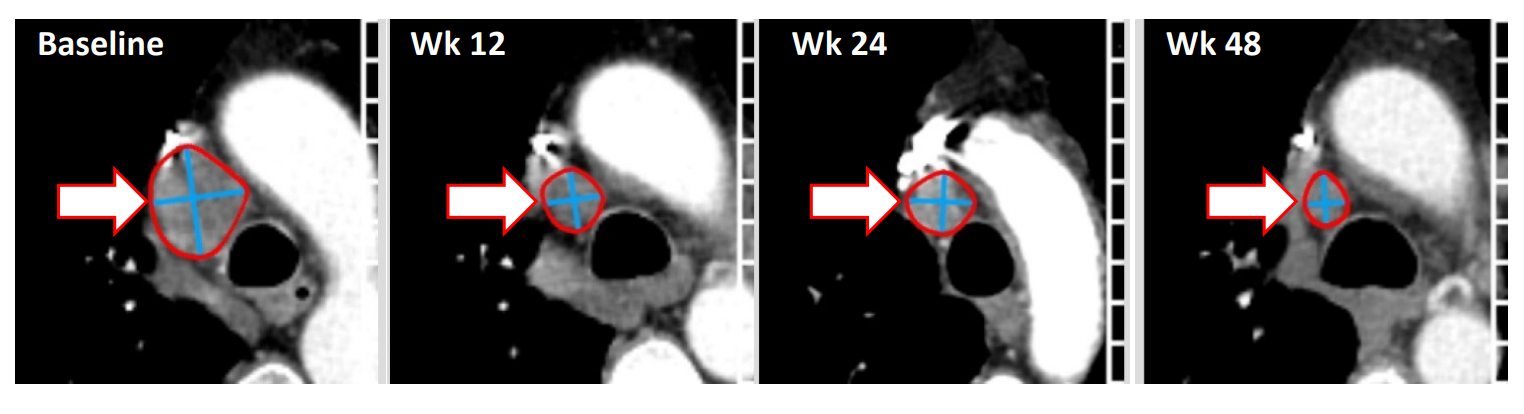

随着技术水平不断提升,人们对癌症的探索逐渐深入,癌症治疗的策略也在不断改变。而近年来,利用免疫系统来对抗癌细胞被发现是一种非常具有潜力的治疗方式。其中肿瘤浸润淋巴细胞(TIL)疗法已成为一种有前途的实体瘤治疗策略,并在2024年被批准用于既往接受过免疫检查点抑制剂和BRAF/MEK靶向治疗(如适用)的晚期黑色素瘤患者。